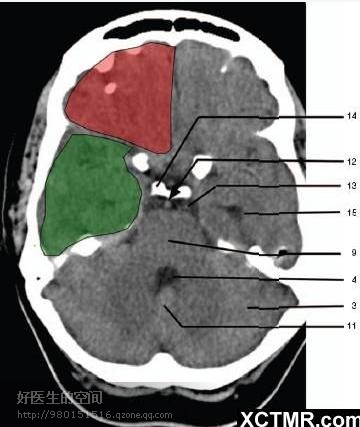

11、小脑蚓部(Cerebellar vermis) 12、基底动脉(Basilar artery) 13、桥前池 (Prepontine cistern) 14、鞍背 (Dorsum sellae) 15、侧脑室颞角(Temporal horn of lateral ventricle) 绿色部分为颞叶(Temporal Lobe),浅红色部分为额叶(Frontal Lobe)